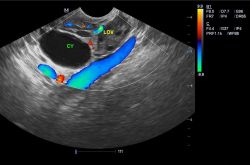

卵巢囊肿怎么治疗最好方法?卵巢囊肿的症状

卵巢囊肿是发生在女性身上的一种疾病症状,其生长在卵巢内的一个像肿瘤一样的小包,里面有着液体,但是并不会对身

卵巢囊肿的治疗方法 卵巢囊肿的症状有哪些

生活中,女性总有大大小小的妇科疾病困扰。如今有很多女性都患有卵巢囊肿,其实这与人们如今的生活习惯是分不开